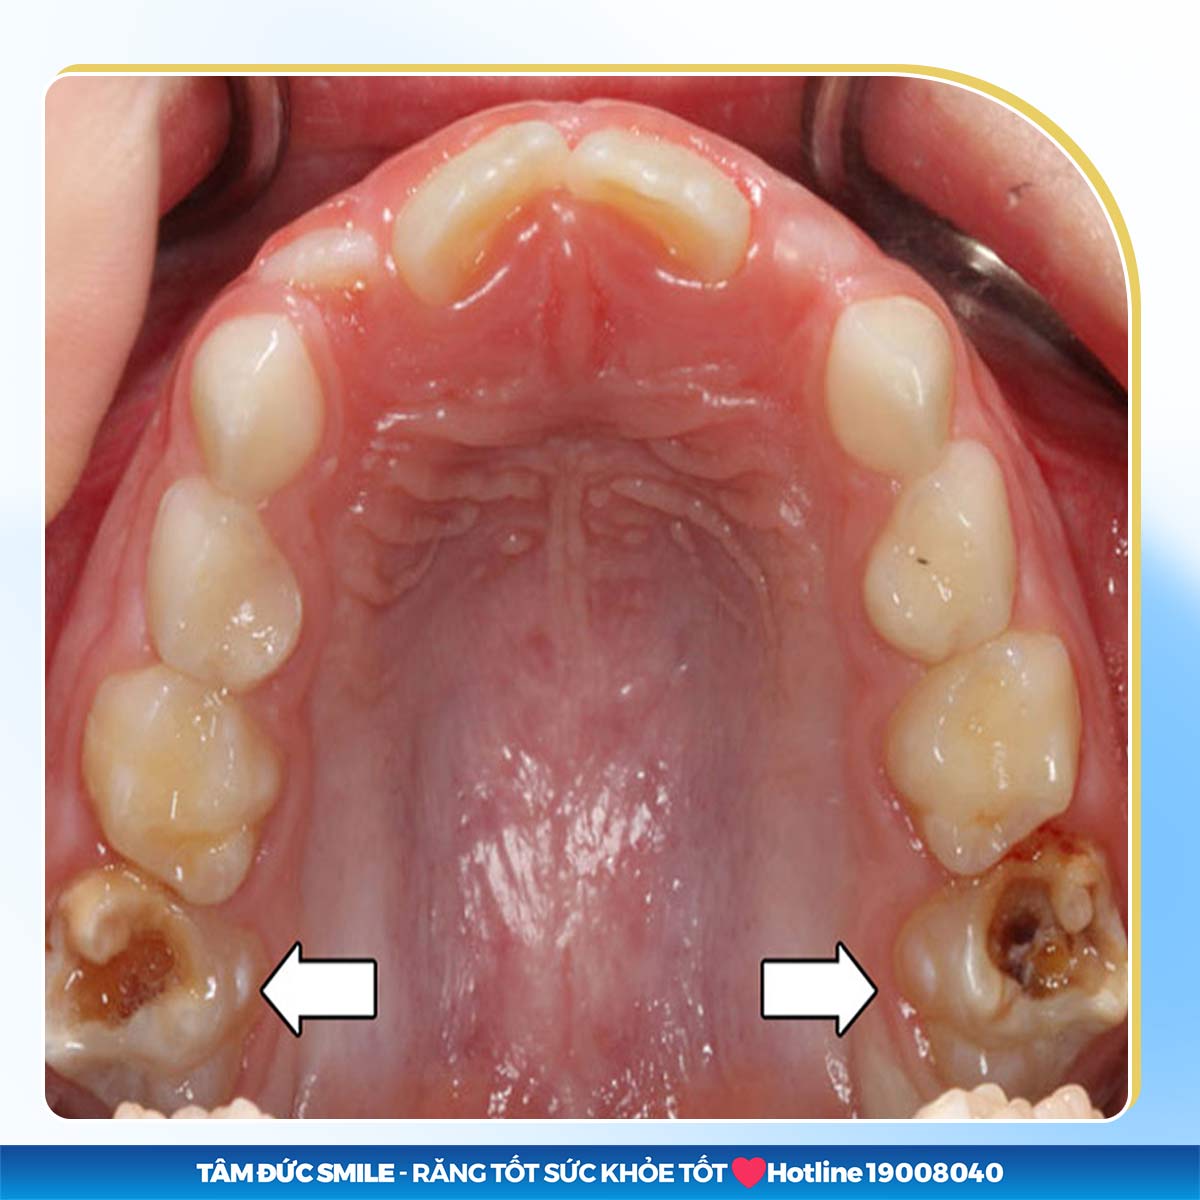

2.1. Sâu răng

Nguyên nhân phổ biến gây mất răng số 6 là do chăm sóc răng miệng không tốt gây sâu răng. Tình trạng sâu răng nặng sẽ khiến men răng và ngà răng số 6 bị phá huỷ, làm cho răng bị hỏng dần từ ngoài vào trong.